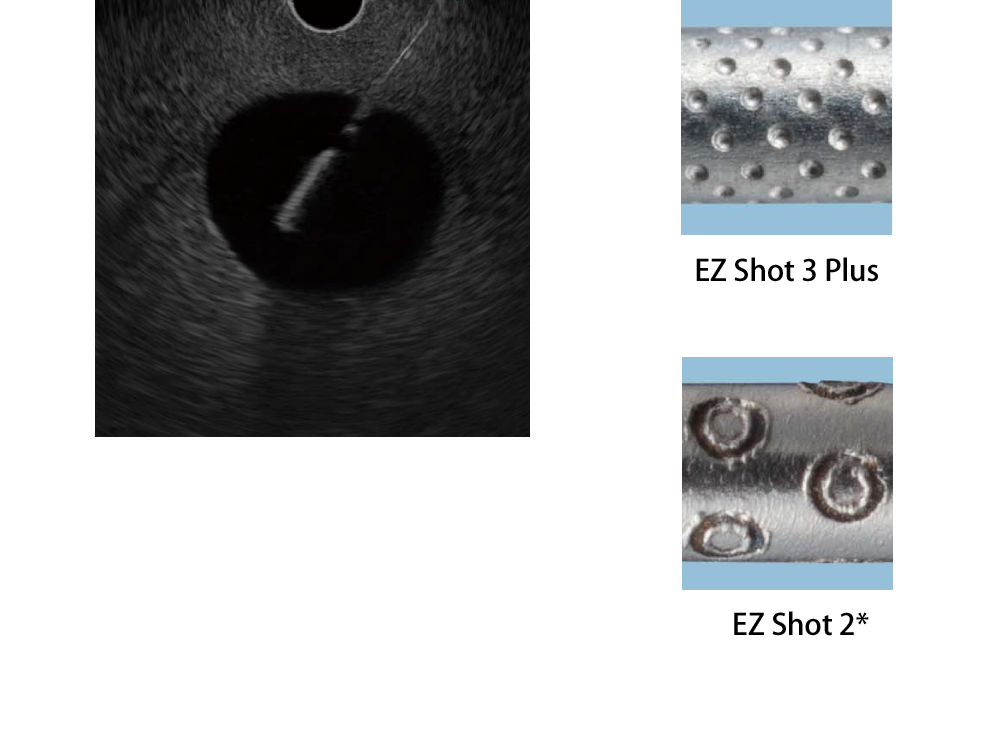

視認性:ディンプル加工の改良による視認性の向上

針先端表面のディンプル加工を改良。半球状のエコージェニックパターンを高密度に配置して、高い視認性を追求しています。

*ディスポーザブル吸引生検針 NA-220H/230H